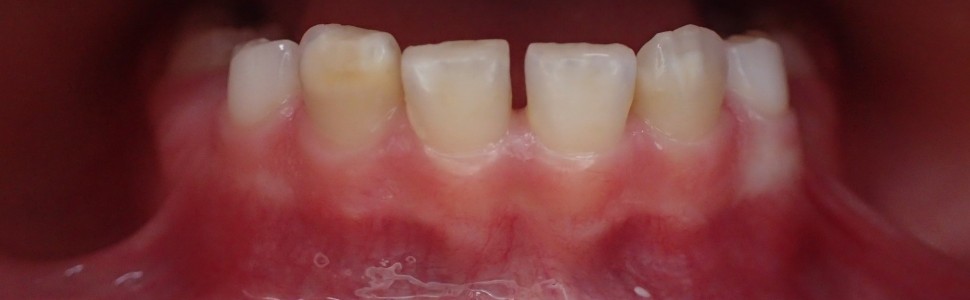

Wstęp. Hipomineralizacja trzonowcowo‑siekaczowa to jakościowy defekt szkliwa, który dotyczy co najmniej jednego stałego pierwszego zęba trzonowego oraz może obejmować stałe zęby sieczne.

Wyniki. Z doniesień piśmiennictwa wynika, iż etiologia nie została do końca poznana. Bierze się pod uwagę wpływ czynników środowiskowych, ogólnoustrojowych i genetycznych. Klinicznie obserwuje się zmiany w postaci nieregularnego zmętnienia szkliwa, zęby te przejawiają większe ryzyko rozwoju próchnicy, patologicznego starcia i nadwrażliwości.

Introduction. Molar incisor hypomineralization is a quality defect of enamel, which affects at least one first permanent molar tooth and sometimes permanent incisors.

Results. The etiology isn’t fully understood. The influence of environmental, systemic and genetic factors is taken into account. Changes in the form of irregular enamel clouding are clinically observed, affected teeth show greater risk of caries, pathological abrasions, hypersensitivity.